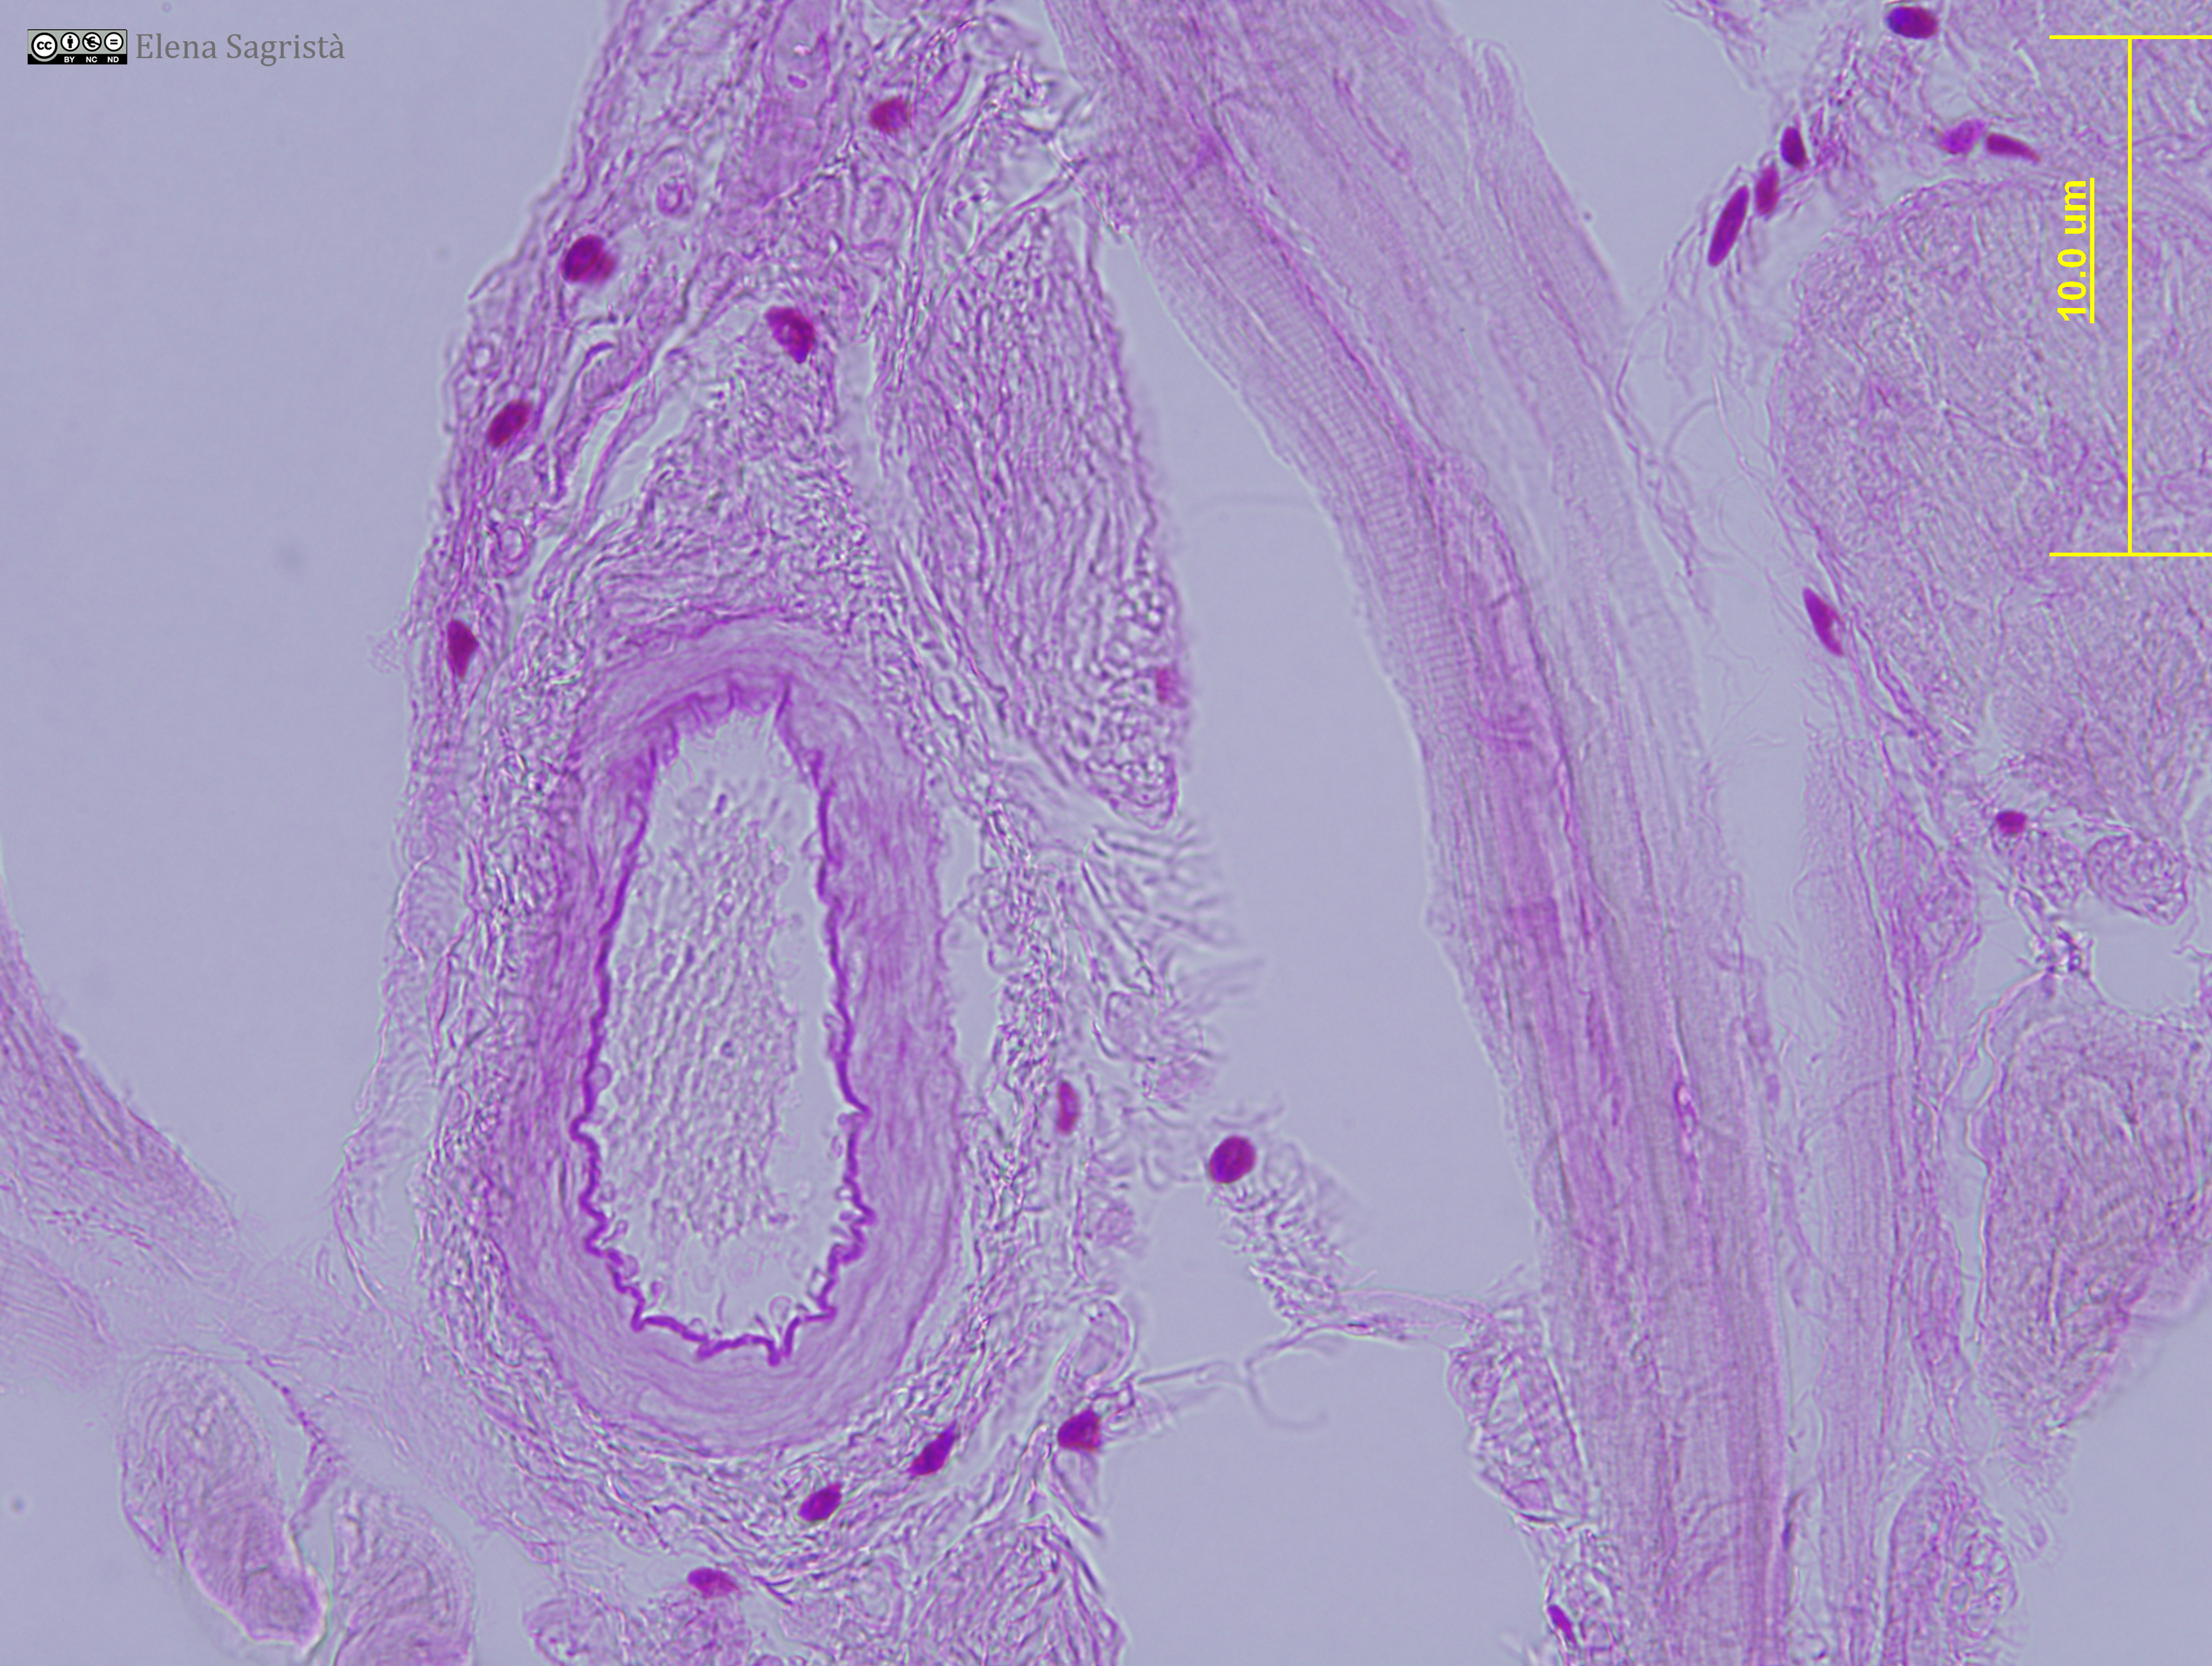

Histologia imatges: 02 Teixit conjuntiu

Imatges de preparacions histològiques de Teixit conjuntiu. Microscopia òptica.